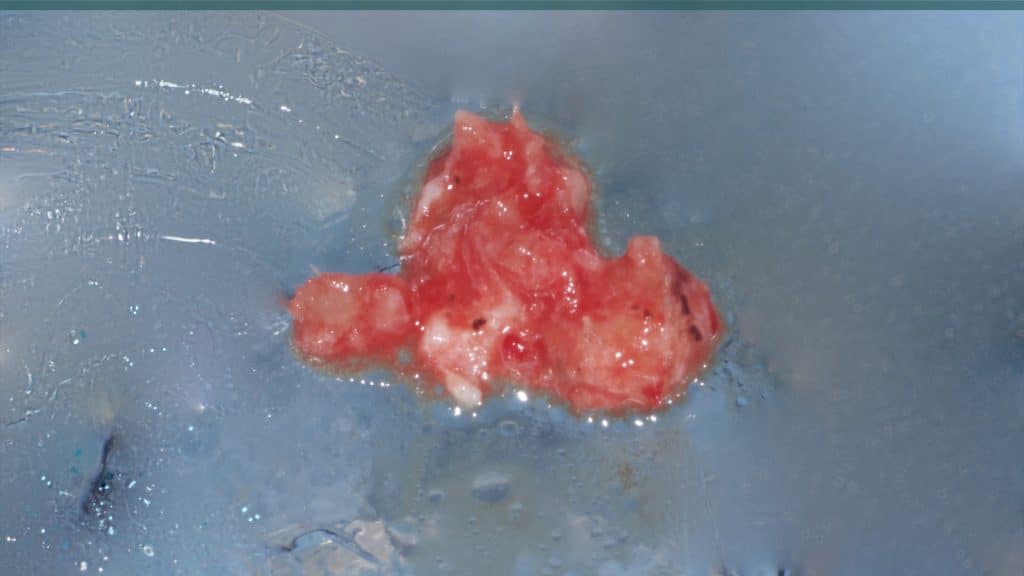

A 27-year female patient with dislodged Resin bonded FPD. She had that FPD for past few years, it had metal wings on palatal surfaces of UR1 and UL2 and a post like metal extension into the root canal of UL1. There was gingival abscess due to fractured root segment most probably due to extended metallic post like structure. Immediate implant placement (IIP) and Immediate restoration (IR) was planned for this patient.